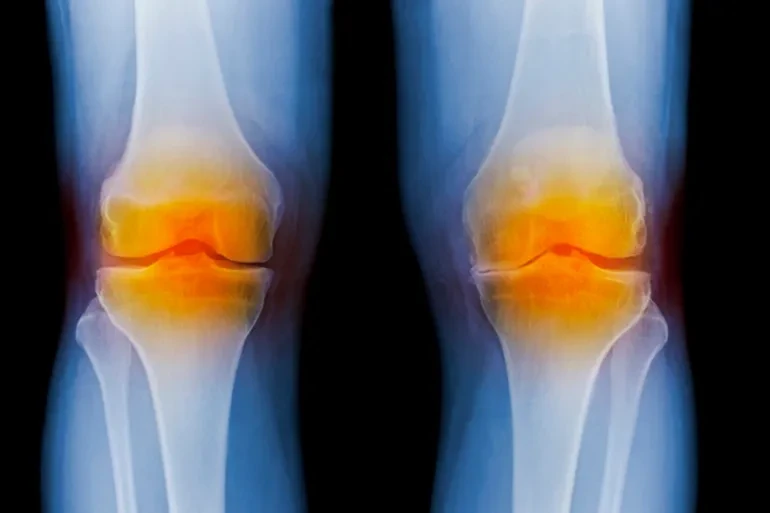

أصبحت الإصابة بالخشونة والآلام المزمنة في الركبة آفة تهدد نحو نصف عدد البشر (حسب الإحصائيات) خاصة مع تقدم العمر، وفي السطور التالية نحاول الإجابة عن السؤال الذي يراود الكثير من الناس: كيف نتجنب الخشونة ونمنع آلام الركبة؟

وخشونة الركبة مصطلح عام، غير علمي، يشير إلى إصابة الركبة بمرض الفصال العظمي (Osteoarthritis).

تحدث خشونة الركبة عندما يتآكل الغضروف في مفصل الركبة، فتحتكّ العظام بمفصل الركبة مما يتسبب في احتكاك يؤدي إلى إصابة ركبتيك بألم أو تصلب أو تورم، وهي حالة شائعة جدا، فما يقرب من 46% من الناس سوف يصابون به خلال حياتهم، وفق كليفلاند كلينيك.